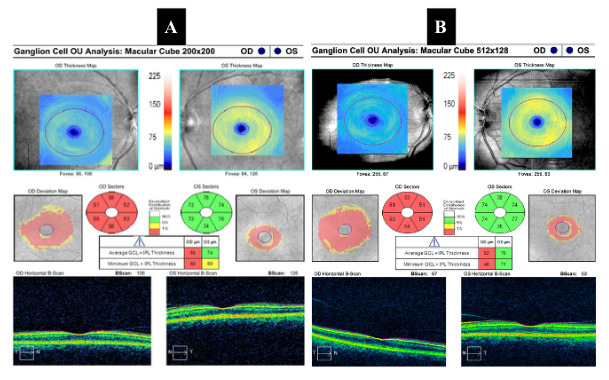

Her laboratory workup was unremarkable for any inflammatory or infectious etiologies. Her brain magnetic resonance image with and without contrast revealed scattered nonspecific punctate and patchy foci of T2 hyperintense signal without mass effect in the bilateral subcortical and periventricular white matter and corona radiata, likely due to minimal chronic microvascular ischemic changes. The report also stated T2 hyperintense signal present in the cortex of the posterior left frontal lobe with associated volume loss likely reflecting small chronic infarction. An exact etiology for her vision loss in the right eye was not noted on the magnetic resonance image brain report. However, upon review of the images and discussion with the radiologist, it was determined that there was some increased T2 signal around the right optic nerve. A dedicated orbital magnetic resonance image with and without contrast was ordered. The orbital magnetic resonance image revealed a 9 × 11 × 5 mm type III anterior clinoidal meningioma extending into the optic canal along the optic nerve sheath (Figure 5). Based on these findings, she was scheduled to see a neurosurgeon and underwent a right fronto-orbital craniotomy with tumor resection which was completed without complications. She also discontinued medroxyprogesterone therapy.